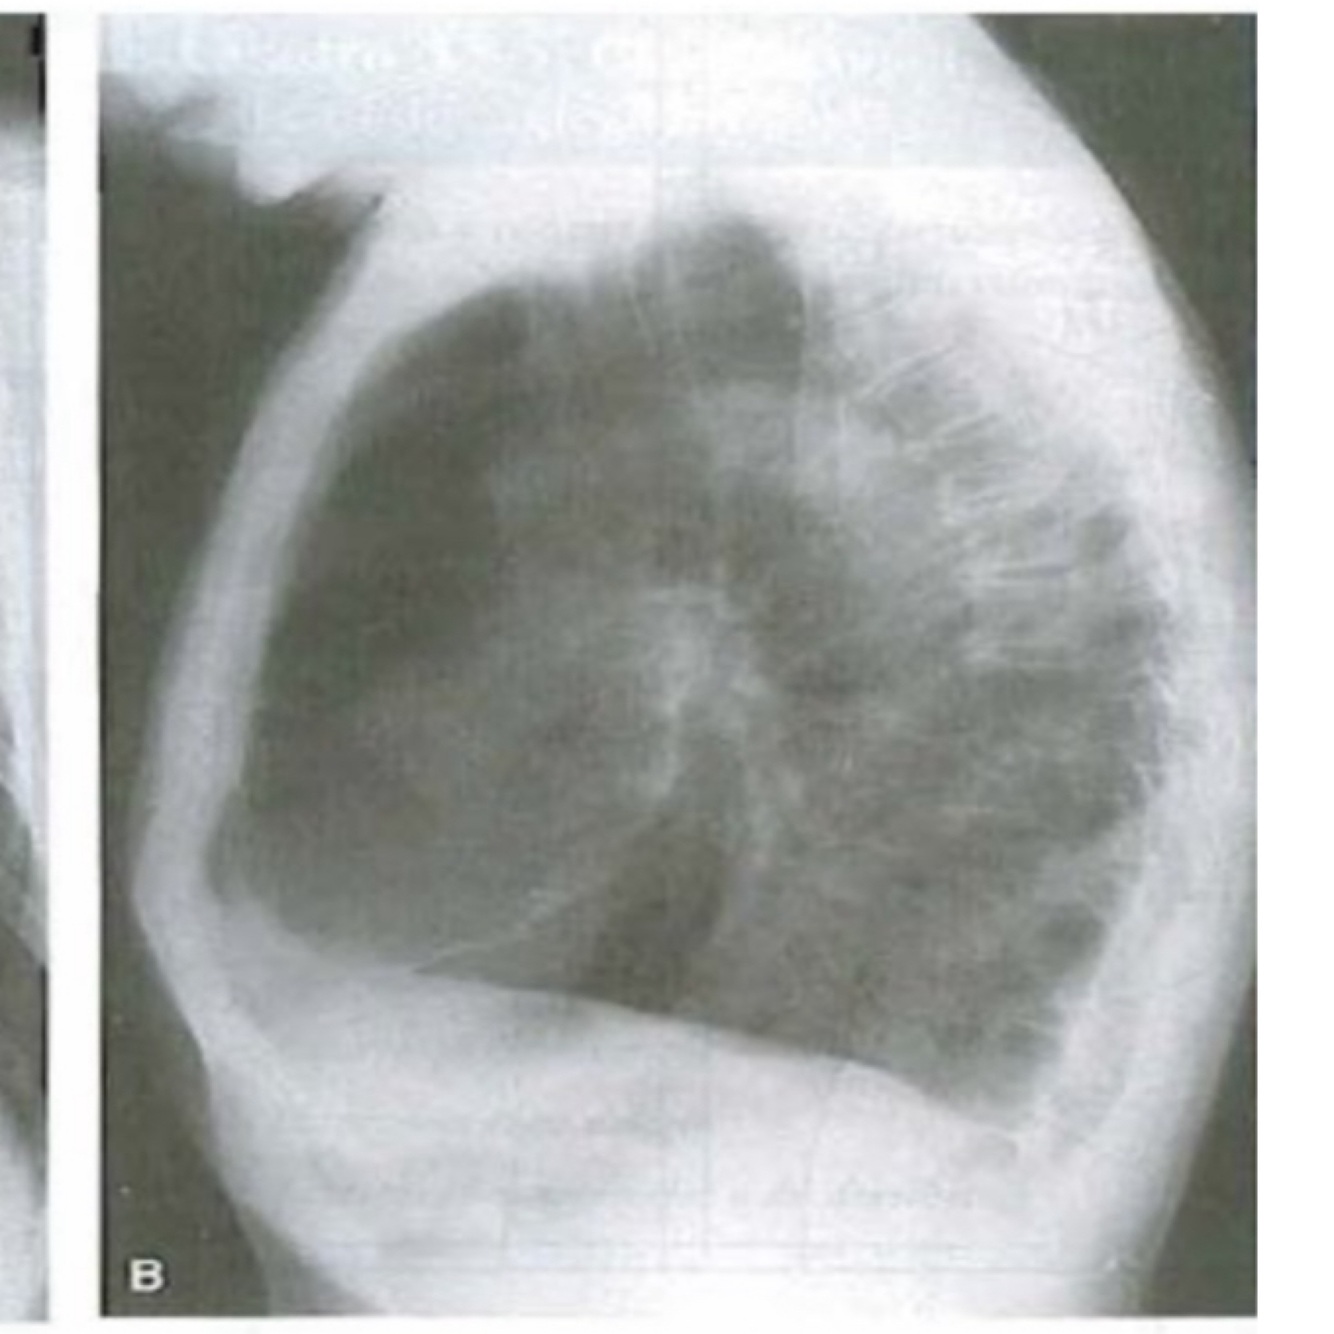

Q

A

enfisema pulmonar